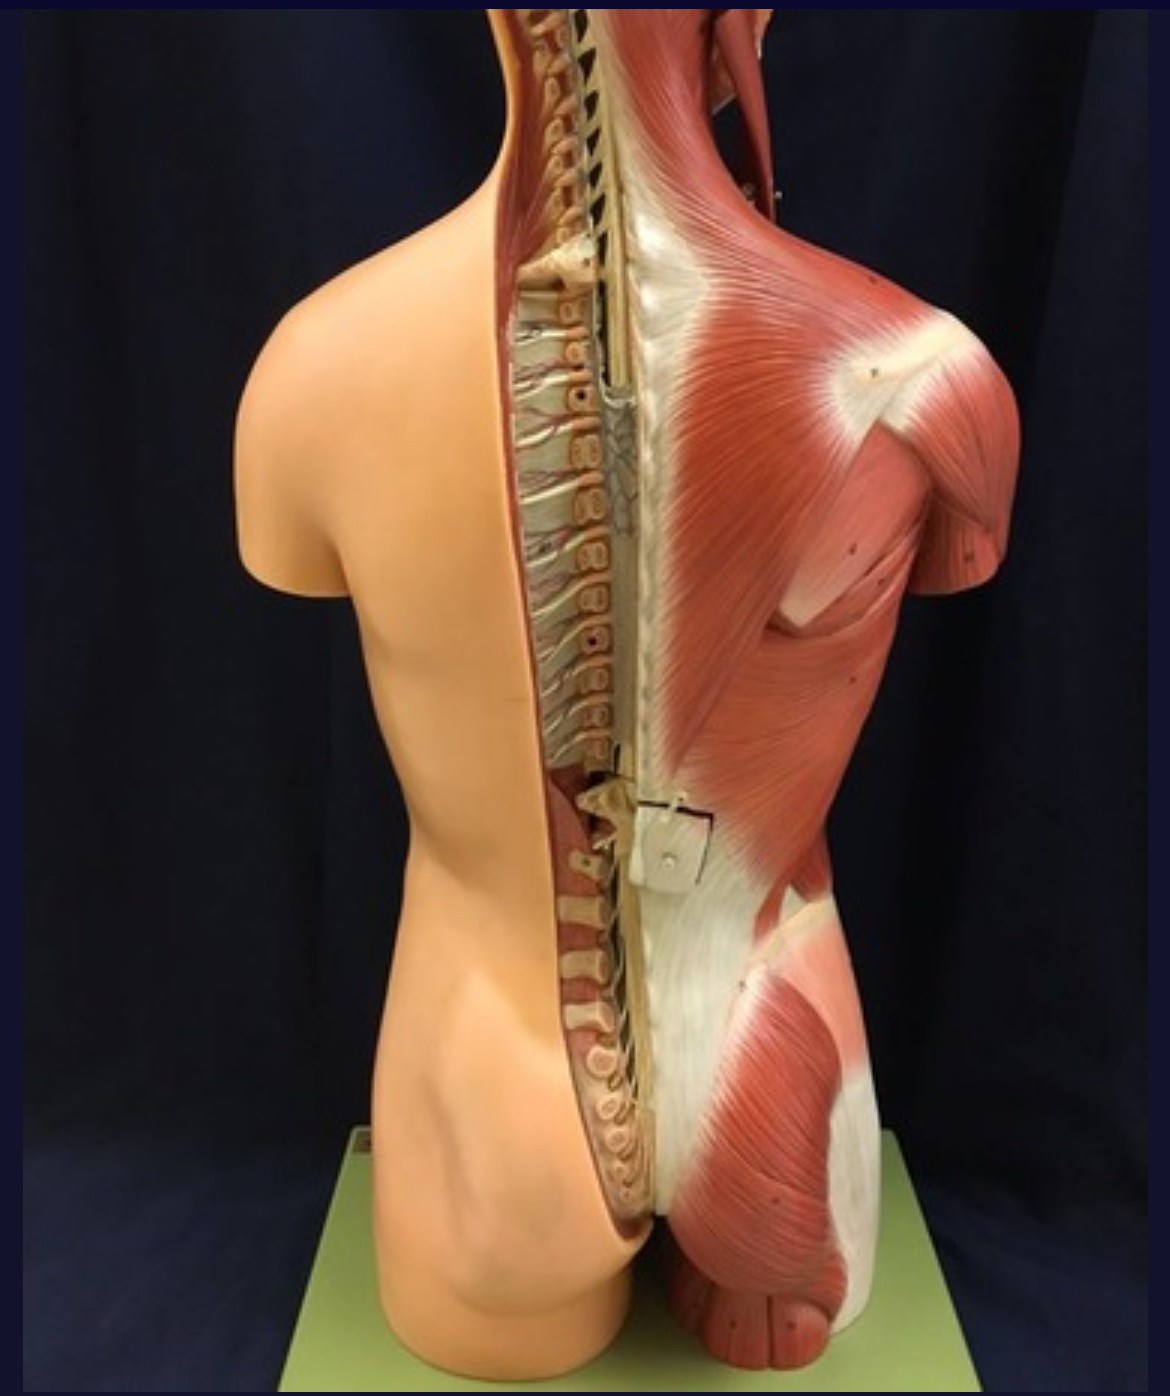

Spinal cord

Cauda equina

White matter of spinal cord

Gray matter of spinal cord

Ventral horns (of gray matter)

Lateral horns

Dorsal horns

Anterior columns of white matter

Lateral columns of white matter

Posterior columns of white matter

central canal of spinal cord

Dorsal Ramus

Ventral ramus